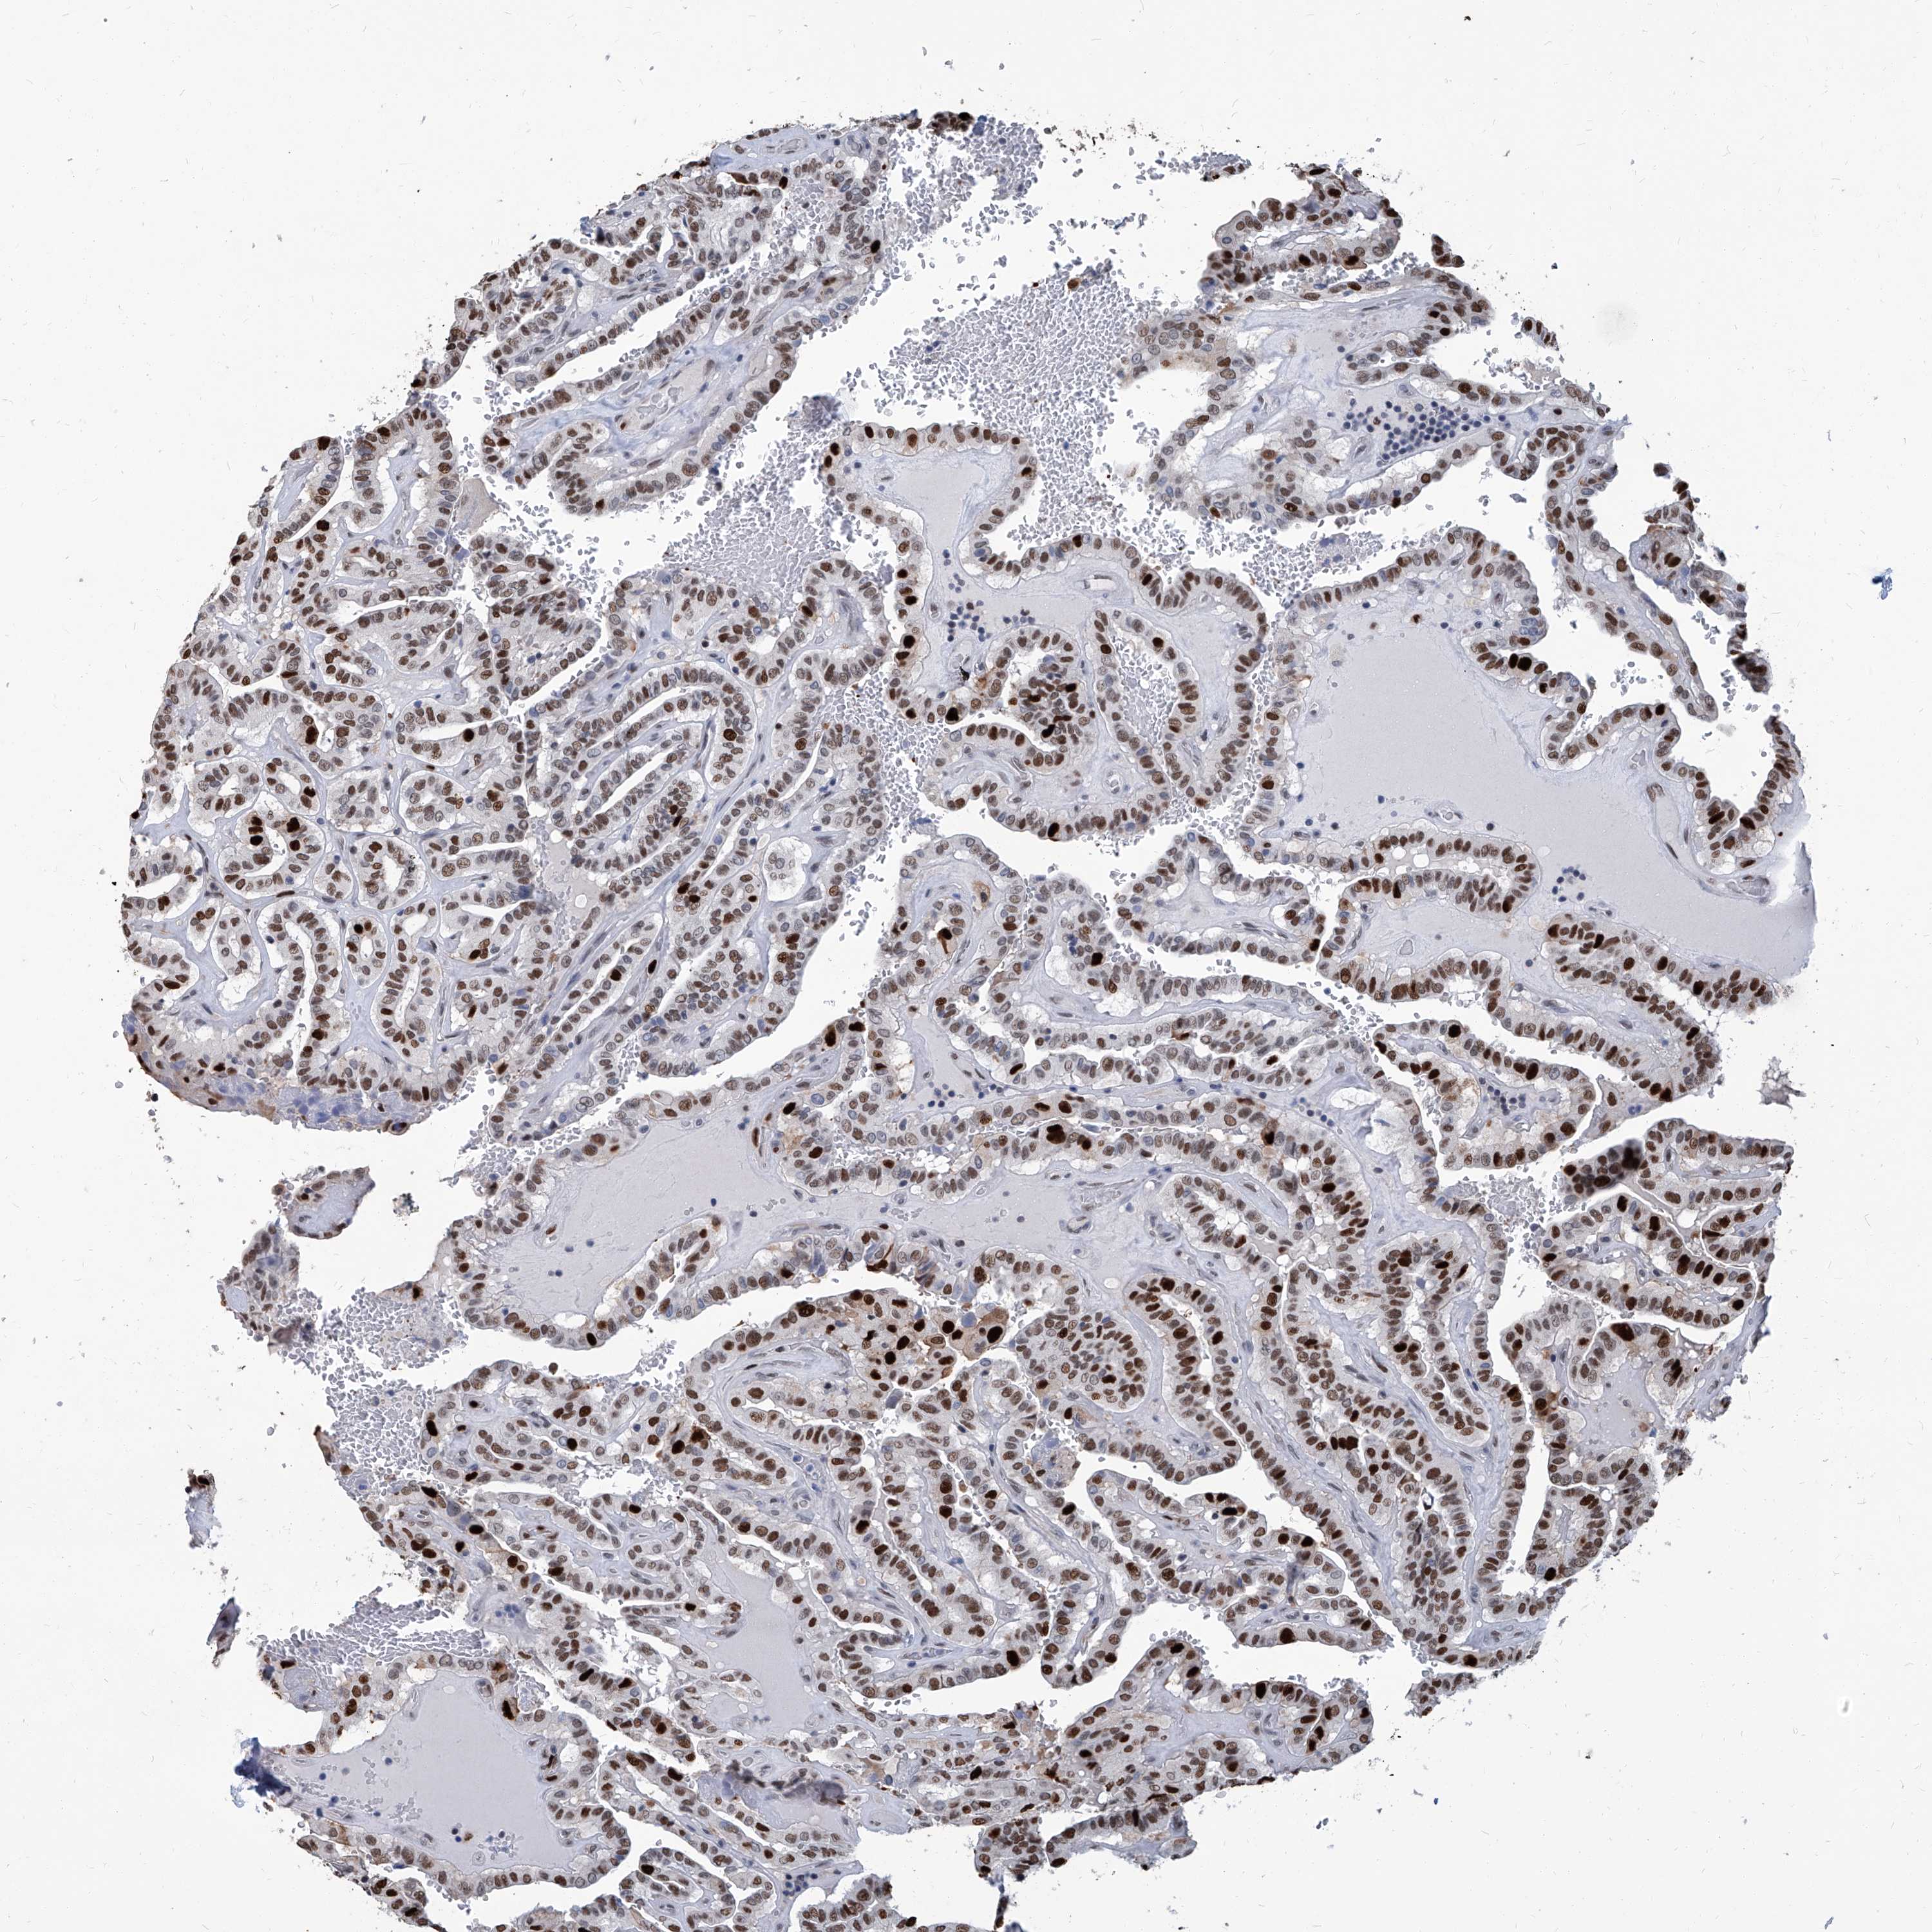

THYROID CANCER - Protein expressioni

A mouse-over function shows sample information and annotation data. Click on an image to view it in a full screen mode. Samples can be filtered based on level of antibody staining by selecting one or several of the following categories: high, medium, low and not detected. The assay and annotation is described here.

Note that samples used for immunohistochemistry by the Human Protein Atlas do not correspond to samples in the TCGA dataset.

Antibody stainingi

Antibody staining in the annotated cell types in the current human tissue is reported as not detected, low, medium, or high, based on conventional immunohistochemistry profiling in selected tissues. This score is based on the combination of the staining intensity and fraction of stained cells.

Each image is clickable and will lead to virtual microscopy that enables deeper exploration of all samples and also displays staining intensity scores, fraction scores and subcellular localization as well as patient and tissue information for each sample.

Papillary adenocarcinoma, NOS

Follicular adenoma carcinoma, NOS

Carcinoma, NOS